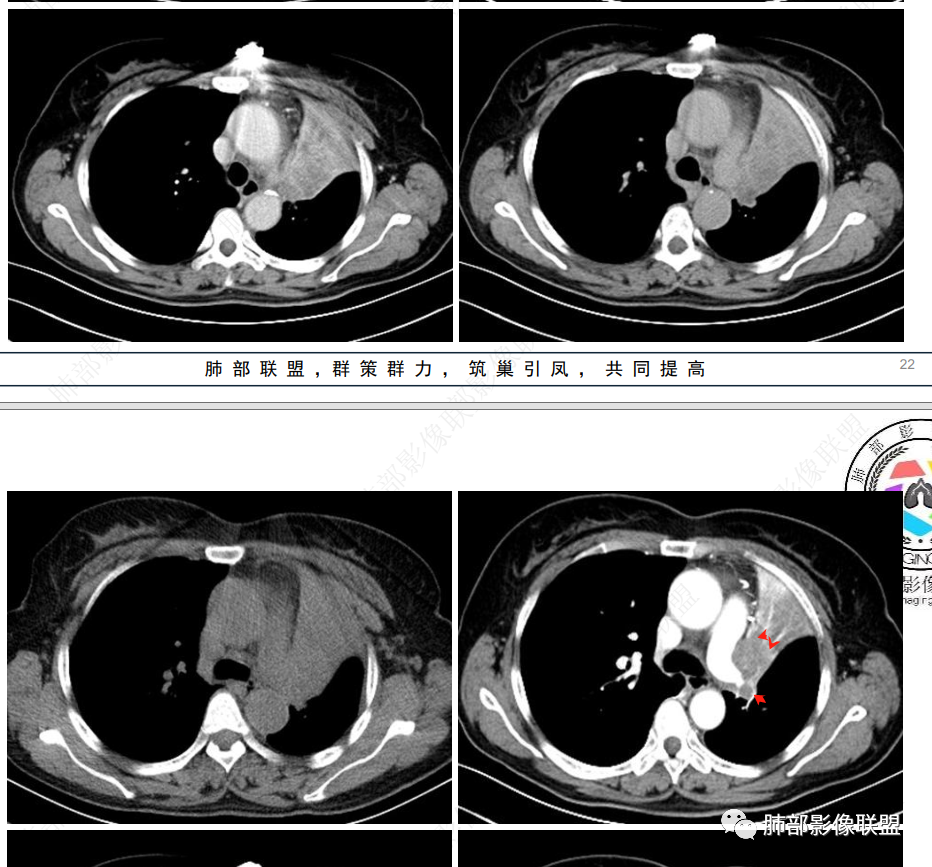

2、影像表现:正常肺背景,左肺上叶支气管腔内占位,上叶支气管截断,远端肺组织不张,强化差异衬托出肺门区结节影或块状影。增强扫描腔内占位轻中度不均匀强化,可见坏死,远端粘液栓,局部肺动脉受压、侵犯,纵膈淋巴结无明显肿大,无胸腔积液。

3、综合分析:老年女性,支气管腔内占位明确,病灶向周围侵犯,诊断恶性肿瘤并肺不张问题不大。需要考虑到的疾病谱有鳞癌、腺样囊性癌、粘液表皮样癌、类癌、小细胞肺癌等。